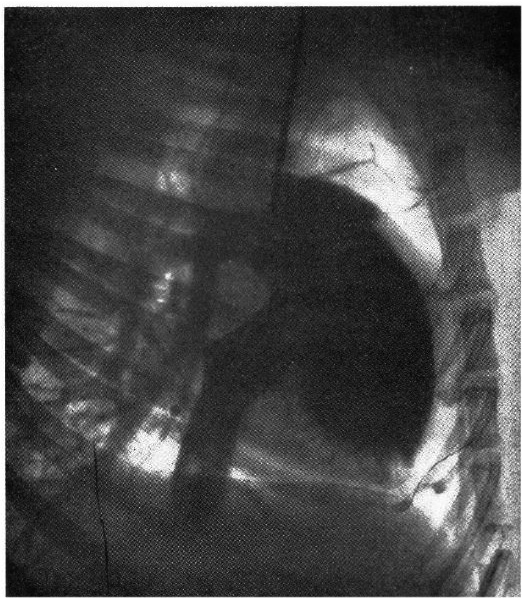

図2. カテーテル法によるイヌの心腔造影.自己人体実験では造影効果が得られず,失敗に終わった.

【要旨】 上肢静脈から造影剤を投与して上大静脈~心腔を造影することには誰も成功していない.そこで,前年に自分が報告した右心系へのカテーテル挿入法を拡張して造影を試みた.前報の後,22例にカテーテル挿入を試み,15例で成功した(図2).動物実験で心腔が造影されることを確認し,再び自己人体実験を試みた.

1回目は,左肘静脈から8Fの心臓カテーテルを挿入し,25%ヨウ化ナトリウム20ccを急速注入して撮影し,肺動脈の画像が得られたが心腔は見えなかった.注入後まもなく軽度のめまいがあったがすぐ消失した.1日半にわたってヨウ素による鼻閉感,味覚障害があった.2回目は,右大伏在静脈から8F尿管カテーテルを挿入し,Uroselectan(ウロセレクタン)を20cc注入したが,技術的な理由によりX線撮影はできなかった.

動物実験の観察では,心腔の形態は心房収縮期,心室収縮期,静止期の3時相が区別され,それぞれ形態が異なっている.

【解説】 右心系にカテーテルを挿入する前掲の第一報は予想に違わず大きな批判を受けたが,その続報として再び自らを実験台にして心腔造影を試みた論文である.動物実験では造影写真が得られたが,自己人体実験での撮影には失敗した.ここで述べられている自己人体実験は2回であるが,実際には9回行なってすべて失敗したらしい.論文の後半には,お茶を濁すように動物実験における心腔形態の観察結果が述べられている.この論文発表の直後,Forssmannは医学界から追放された.